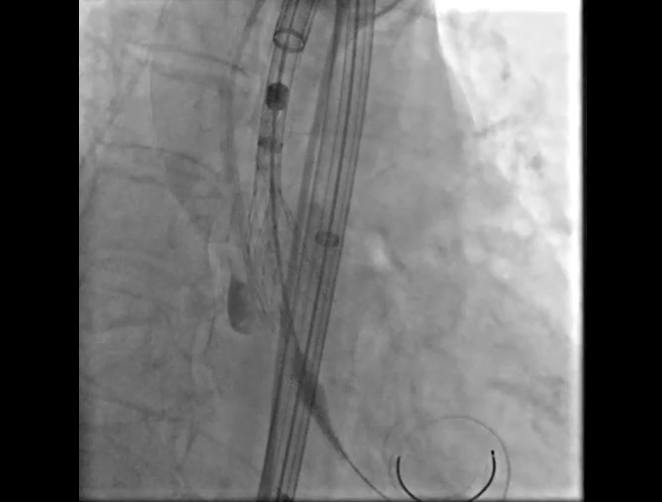

Step 4.输送系统进入:过弓性能优异,悬空通过,整体过程未将鞘管顶起至弓顶部

17.gif